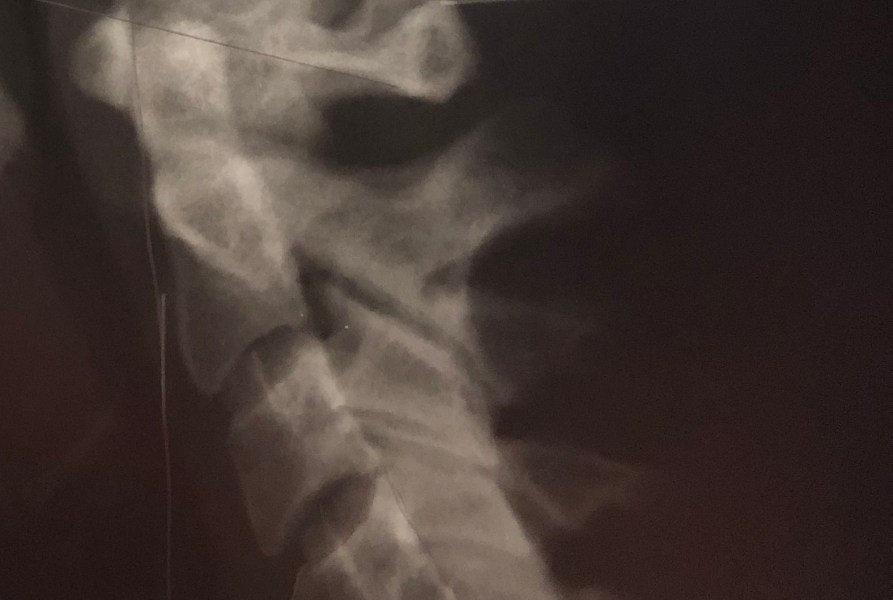

NUCCA – not your mama’s chiropractic

I've been seeing a chiropractic specialist for about 5 years. NUCCA doctors specialize and only adjust the atlas (the first vertebrae at the top of the neck). However they do it in a non-invasive manner that you honestly barely feel. There's no manual cracking, there's no twisting of the neck and back, there's no popping…